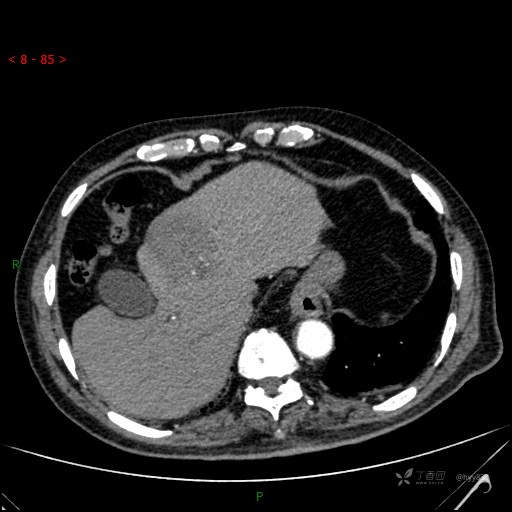

肝脏CT平扫

img